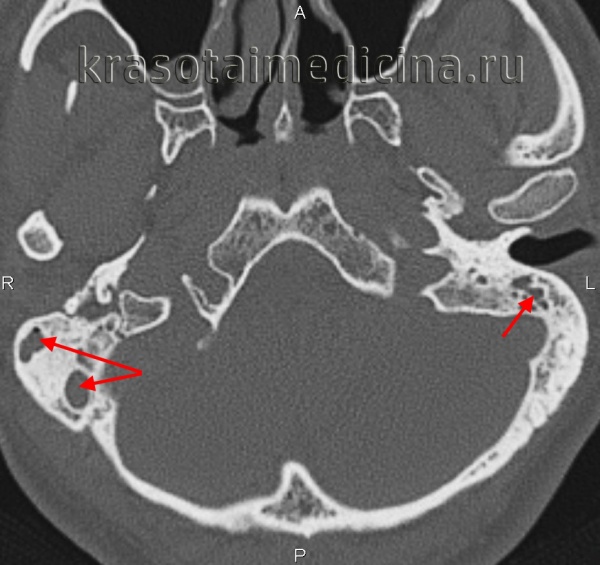

КТ височных костей. Тотальное снижение пневматизации ячеек сосцевидного отростка с обеих сторон. (фото Вишняков В.Н.)